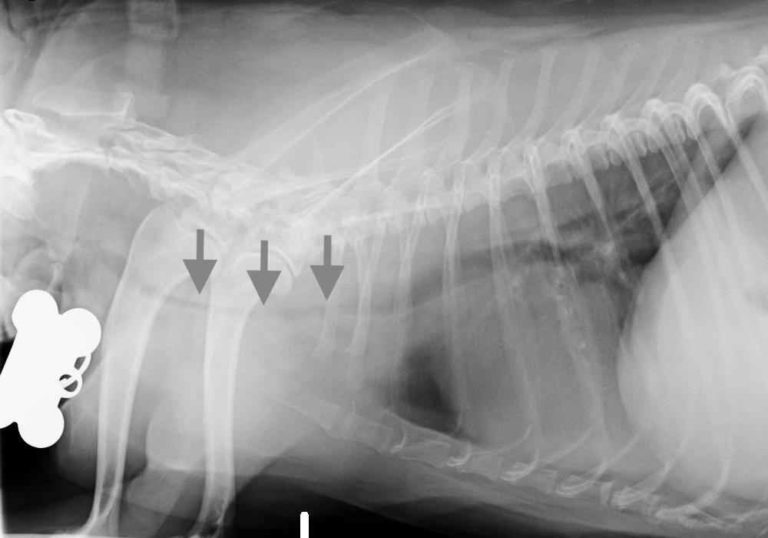

Tracheal Collapse in Dogs a Complete Guide — Our Pet's Health